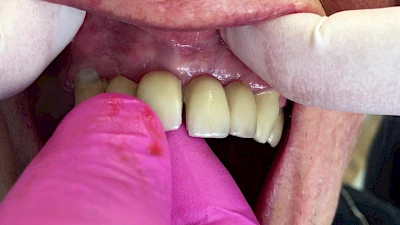

Eine geringe spürbare Beweglichkeit der Zähne ist durchaus normal, da Zähne über Fasern im Kieferknochen aufgehängt sind. Lassen sich Zähne, Kronen oder Brücken jedoch deutlich sichtbar bewegen, besteht die Gefahr, dass sie sich lösen und verschluckt oder aspiriert werden. Deshalb sollte in diesen Fällen der Zahnarzt verständigt werden.